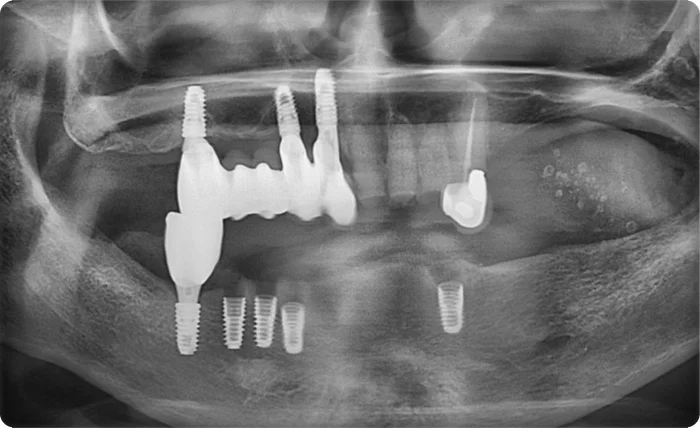

그러다 시간이 지난 뒤 암 4기 진단을 받게 되었고, 치아 통증이 심해져 제대로 씹기조차 어려운 상태가 되어 다시 방문하시게 되었습니다.

하지만 현재 치아 상태로는 단기간에 식사가 편해질 정도로 치료를 마치기도 어려운 상황이었습니다. 치료를 제대로 진행하려면 약 5개월 정도의 시간이 필요한 상태였습니다.